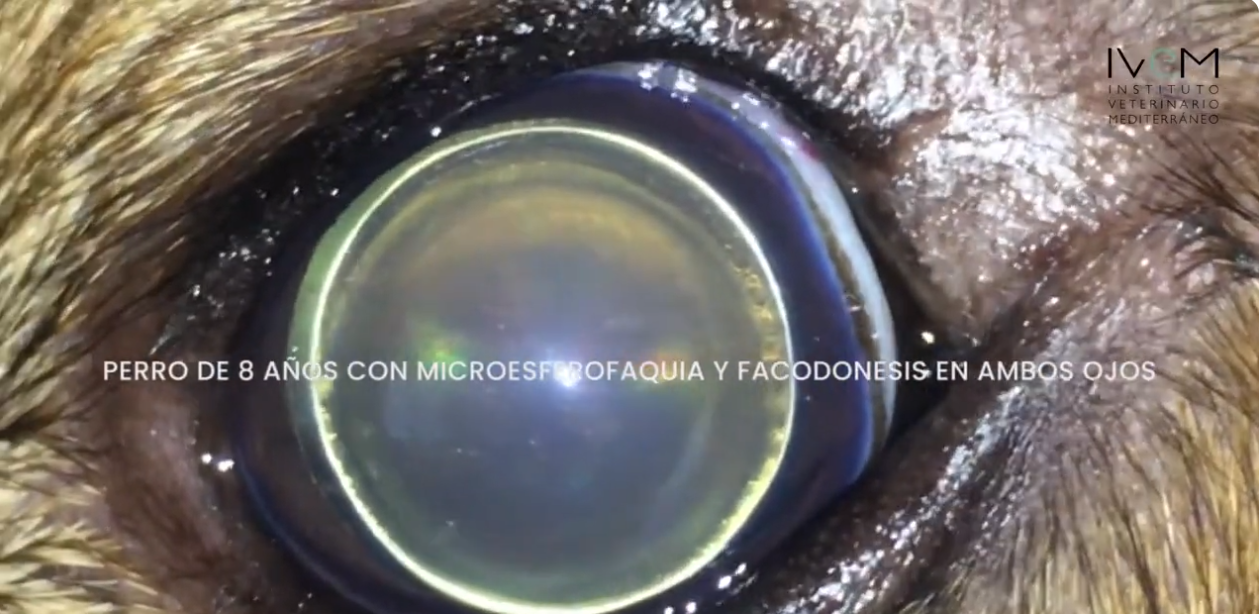

Катаракта у собак: симптомы и лечение. Существует множество причин появления катаракты у собак: неправильное питание, воспаление глаз, травмы и т. д. Однако вполне возможно, что у собаки катаракта разовьется из-за генетических особенностей породы или вследствие диабета. Катаракта у собак […]